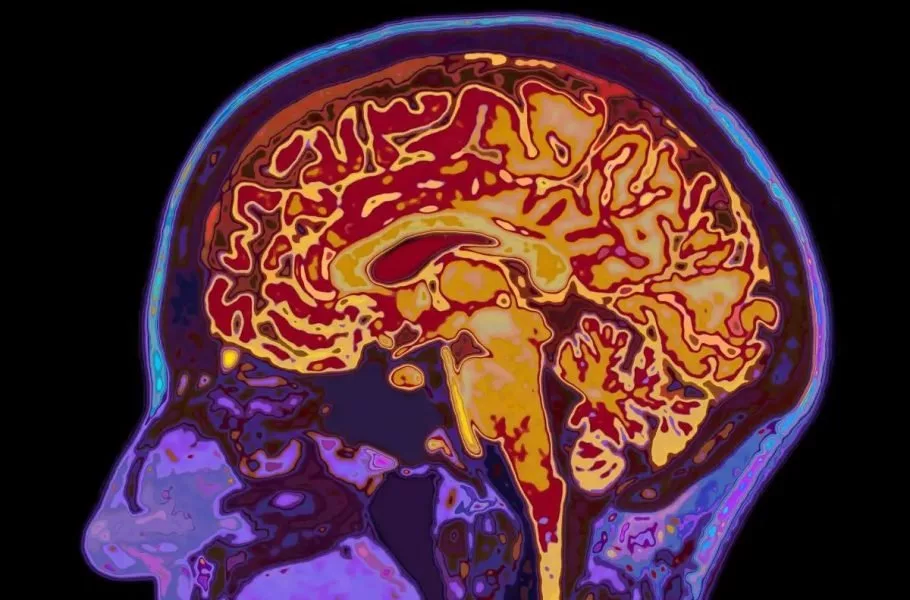

شاید فکر کنید با تمامشدن دوران نوجوانی، مغز شما هم به بلوغ و رشد نهایی رسیده است. اما دانشمندان دانشگاه کمبریج این باور قدیمی را رد کردهاند. آنها با اسکن مغز ۴ هزار نفر (از نوزاد تا ۹۰ ساله) کشف کردند که مغز انسان نه یک مسیر خطی، بلکه ۵ دوران متمایز را طی میکند. محققان میگویند مغز ما تازه در اوایل دهه ۳۰ زندگی وارد فاز بزرگسالی میشود.

تصور رایج این است که نوجوانی در ۱۸ یا ۱۹ سالگی تمام میشود، بااینحال مطالعه جدید نشان میدهد که مغز تا حدود ۳۲ سالگی همچنان در فاز «نوجوانی» باقی میماند. در این دوران طولانی (از ۹ تا ۳۲ سالگی) مغز مشغول سیمکشی مجدد و افزایش بهرهوری است. این همان زمانی است که بیشترین خطر بروز اختلالات سلامت روان وجود دارد، زیرا مغز درحال تغییرات بنیادین است.

به گزارش گاردین، دانشمندان مراحل رشد مغز را براساس ۴ نقطه عطف مهم (در سنین ۹، ۳۲، ۶۶ و ۸۳ سالگی) تقسیمبندی کردهاند: